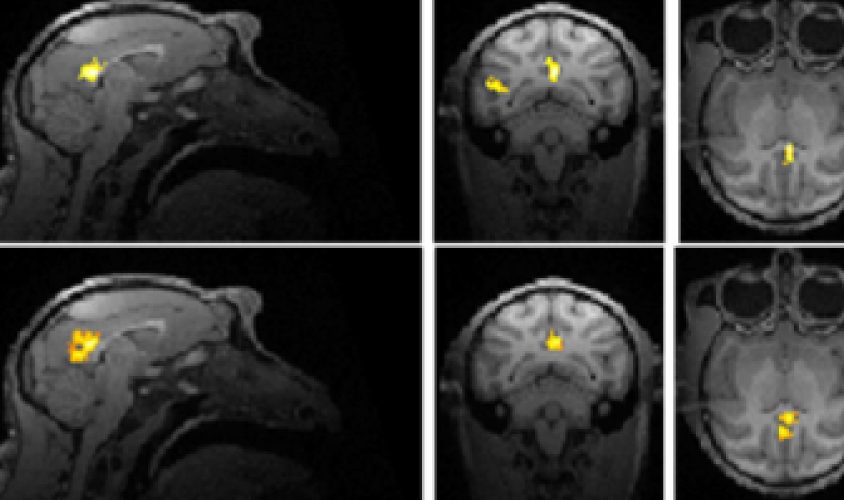

Altered states: Monkeys with a mutation in an autism gene show unusual communication patterns in their brains.

The researchers scanned the monkeys’ brains for coordinated activity between pairs of brain regions, a measure of brain connectivity. The mutant monkeys have unusually low connectivity across some long-range circuits and within two interior brain regions, the thalamus and striatum. They show enhanced connectivity in the somatosensory cortex, which processes sensory stimuli. Some people with autism show similar connectivity patterns.